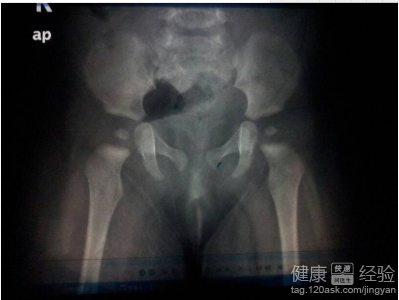

我的女寶寶現2個月21天,2個月8天時兒保發現臀紋不對稱,2個半月做了B超結果如下:雙側髋臼結構清晰,股骨頭位於髋臼中,股骨頭骨化中心未出現。左側髋關節a角約66度,b角約60度;右側髋關節a角約59度,b角約64度。超聲提示左側Graf-Ib型,右側Graf-IIa型。屁股看起來就是一邊大一邊小,我想問,這個結果正常嗎?如果不正常,我們該采取怎樣的糾正措施?

3文中所述的寶寶症狀,左側Graf-Ib型,右側Graf-IIa型.無需處理。I型為正常類型,II型為輕度發育不良,其中IIa型無需處理,IIb型才處理。建議繼續觀察,3個月後復查B超,無需擔心。